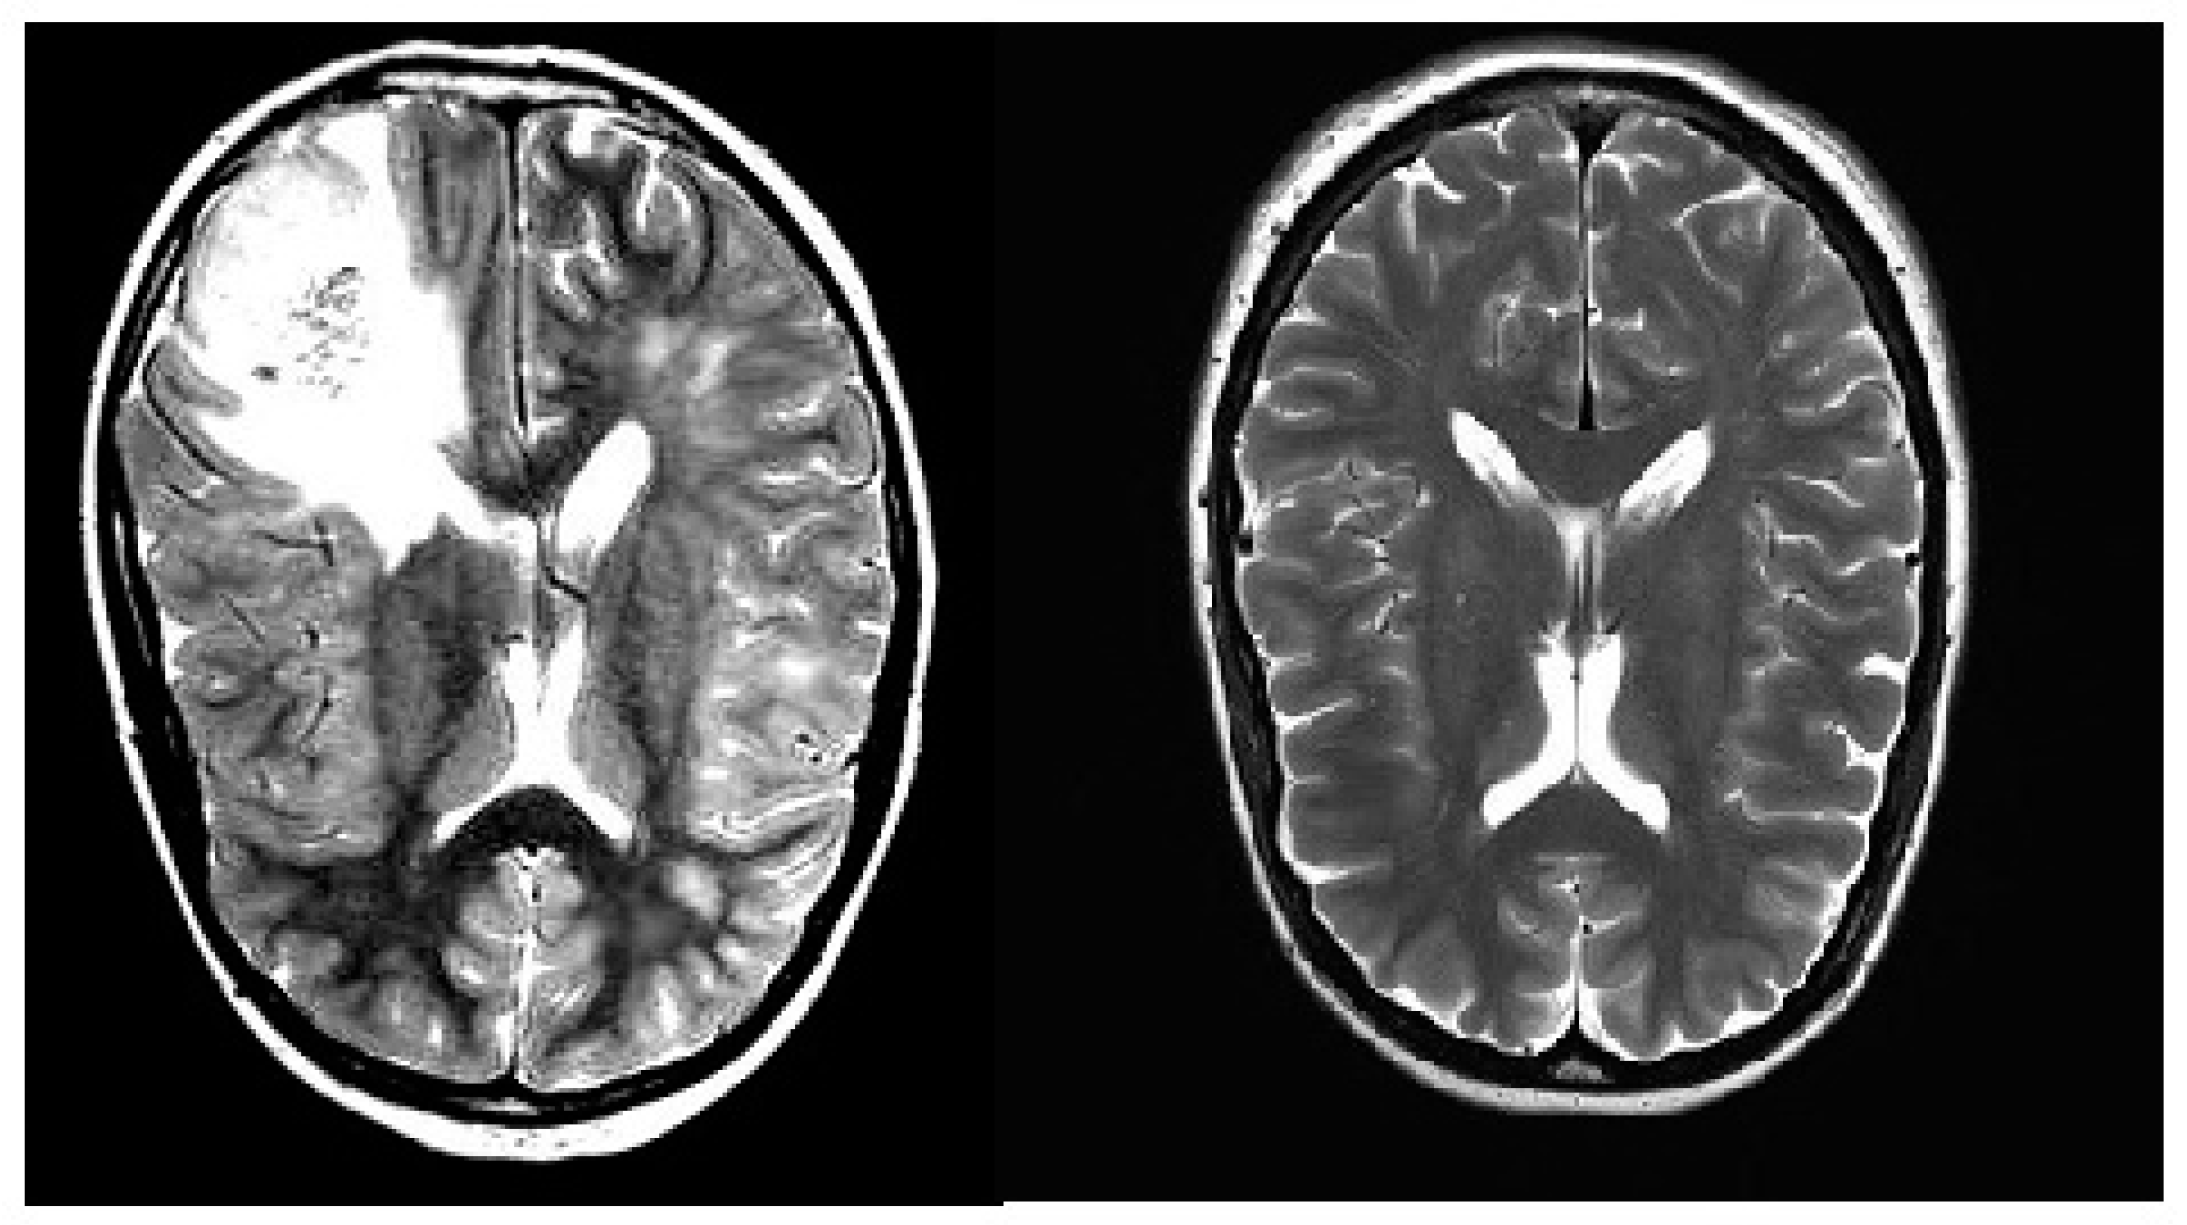

2.1.1. Brain Tumor Detection MRI (BTD-MRI)

2.1.2. Brain MRI Scans for Brain Tumor Classification (BMS-BTC)

2.2. Data Pre-Processing and Augmentation